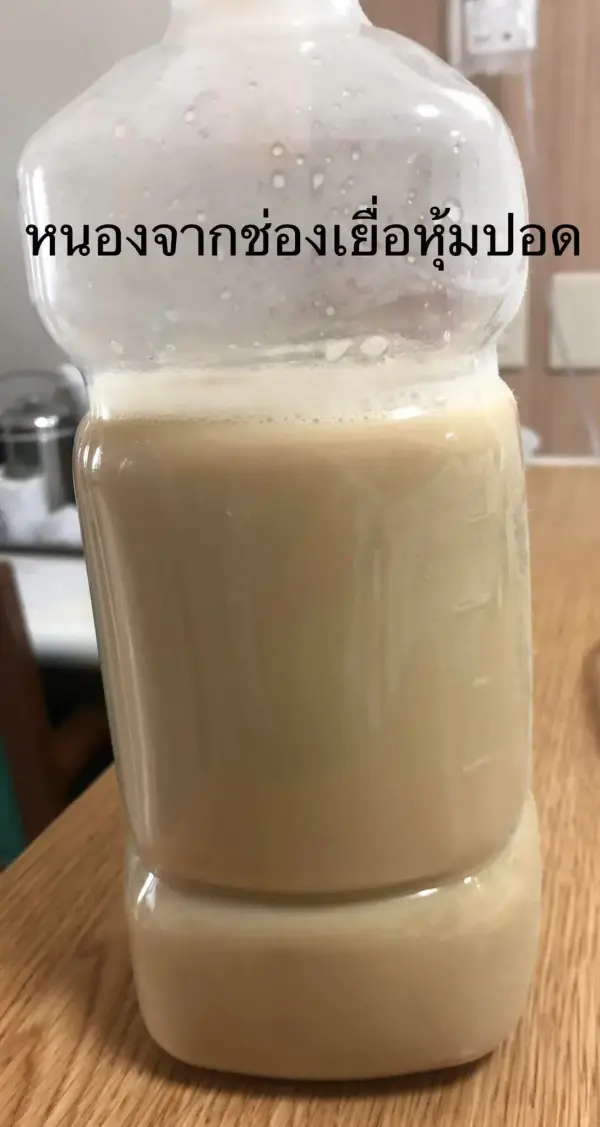

ใส่สายระบายน้ำผ่านทางผิวหนังเข้าเยื่อหุ้มปอดข้างขวา 2 ตำแหน่ง ได้หนองสีเหลืองขุ่น มีกลิ่นเหม็น 1,200 ซีซี (ดูรูป) ย้อมเชื้อพบแบคทีเรียทั้งกรัมบวกและกรัมลบ (gram negative bacilli, gram positive cocci in pairs and chains, gram positive bacilli)